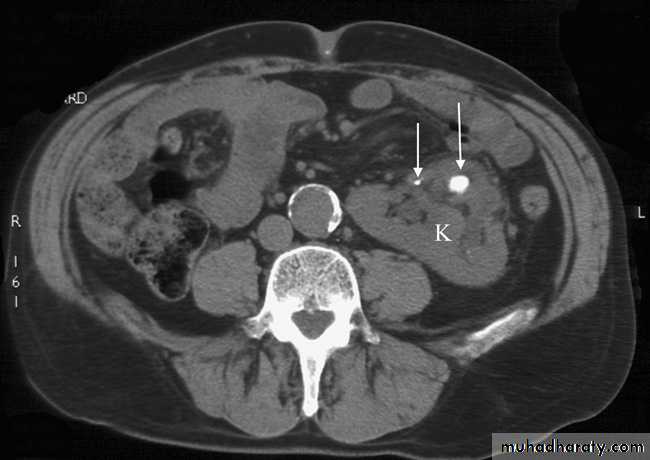

On CT and MRI, a bladder tumour is seen as a soft tissue mass projecting from the wall or a focal thickening of the bladder wall . As the diagnosis is best established by cystoscopy and biopsy, the roles of CT and MRI are to stage the tumour. CT and MRI can determine the spread of tumour beyond the bladder wall and assess lymph node involvement .

Computed tomography does not demonstrate the internal structure of the prostate , so of little value in evaluation prostatic lesion .

Magnetic resonance imaging is best imaging modality for staging , used to assess early stage prostate cancer in patients being considered for radical surgery or radiotherapy. Tumour in the peripheral zone is seen as a relatively low signal mass within the normal high signal of the peripheral zone on T2-weighted images.

MRI is used to demonstrate extracapsular tumour spread, to show invasion of the seminal vesicles, and to demonstrate possible lymph

node metastases .